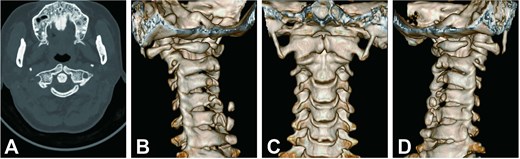

We used a posterior cervical approach to resect the posterior arch of C1. There were no intraoperative complications during the procedure. The patient’s symptoms improved dramatically following the operation. The cervical spinal cord lesion showed no evidence of progression on the 18-month follow-up MRI (Fig. 4A and B). To present, the patient is stable, with no symptoms or signs of recurrence.

Two-year postoperative MRI results. (A) Sagittal T2-weighted MRI. (B) Axial T2-weighted MRI.

CHII lesion is a unique imaging finding defined by Van Dijk et al. in achondroplasia, presenting as hyperintense lesions of the spinal cord on T2-weighted MRI in the absence of local spinal cord compression [4]. According to Khoo et al.’s study, a CHII lesion was found in 47.5% of symptomatic achondroplastic individuals; it appears to be a stable anomaly with no progression or change in morphology [20]. Our case provides evidence for this notion, as the patient’s hyperintense lesions did not change during the 18 months of follow-up after surgery. The finding of CHII lesions in our patient suggests a link between congenital hypoplasia of the atlas and achondroplasia.